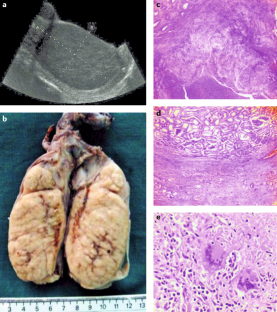

A.Z. receives a UK National Institutes of Health Research (NIHR) senior investigator award. A.Z. acknowledges support from the PANDORA-ID-NET grant from the EDCTP Reg/Grant RIA2016E-1609), CANTAM2, TESA2 and EACCR2 EDCTP Networks of Excellence grants, all funded by the European and Developing Countries Clinical Trials Partnership (EDCTP2) programme, which is supported under Horizon 2020, the European Union’s Framework Programme for Research and Innovation. A.Z. and A.M. acknowledge support from the NIHR Biomedical Research Centre at UCLH. Figures 3a, 3b, 3c, 3d, 3i, 7c, 7d and 7e were kindly provided by Professor Sebastian Lucas, St Thomas’s Hospital, London.